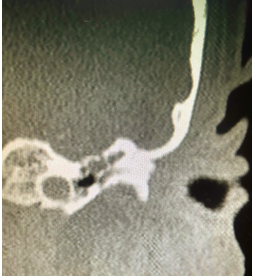

Introduction: Heterotopic Brain and Encephaloceles of middle ear usually present with symptoms of ear discharge and hearing loss. Some patients have additional symptoms of headache, abnormal ringing sensation and vertigo. Radiology may or may not show a communication with central nervous system in encephaloceles and the bony defect may be unnoticeable or attributed to the thinning of bone due to chronic otitis media. On computerised tomography, no distinction may be made between fluid, granulations, cholesteatoma and other space occupying lesions. Morphologically, it may be identified grossly if it presents with its characteristic pink colour and typical convoluted cerebriform pattern (CCP).  Methods: A 26 years female presented to us with unilateral ear discharge since birth and unilateral hearing loss on ipsilateral side for last 18 months. Clinically, radiologically and morphologically it mimicked chronic otitis media with cholesteatoma with no pre-operative and intra-operative distinction from the later. However, the coronal section at the level of anterior tegmen showed a small defect of the tegmen. T2 weighted MRI confirmed presence of brain tissue in middle ear and mastoid cavity. Results: Combined Middle Cranial Fossa and mastoid approach were employed, unviable brain tissue was excised and sent for histopathology. Viable brain tissue was reduced and tegmen defect was closed with temporalis muscle, conchal cartilage and temporalis fascia. Histopathology revealed glial tissue, ependyma and choroid plexus without any cholesteatoma. Conclusion: Tympanic encephalocelesare very rare and may closely mimic chronic otitis media. It may become very difficult to differentiate between the two which may lead to unexpected complications andloss